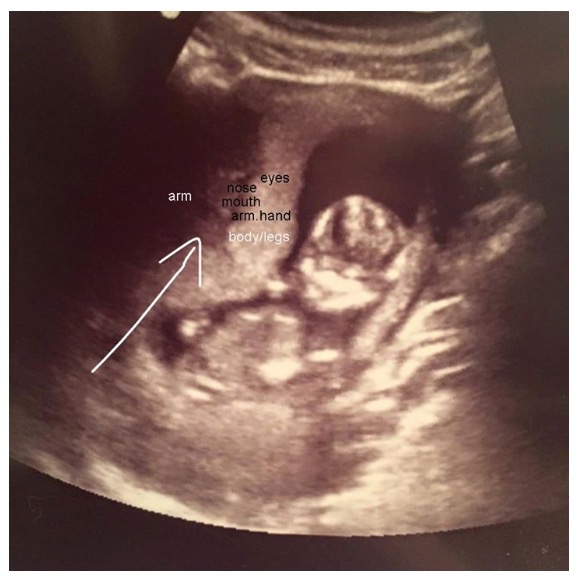

Spoke with a midwife. She sees a baby but a smaller size. This is the photo she sent to me labeled.

Attachment 28474